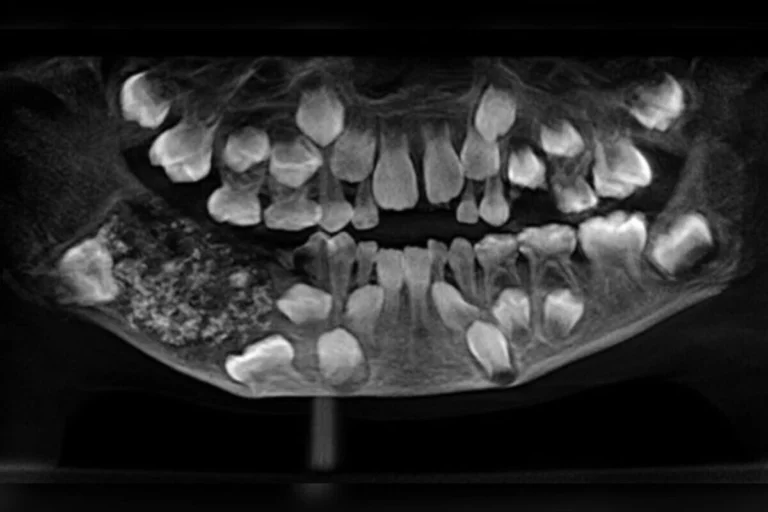

O que parecia apenas um inchaço no maxilar de um menino de 7 anos de Chennai, na Índia, acabou revelando um dos casos mais raros já documentados pela odontologia.

Durante uma cirurgia realizada em 2019, no Saveetha Dental College and Hospital, médicos encontraram 526 dentes em miniatura dentro de uma massa localizada na mandíbula do garoto. Segundo o hospital, os pais haviam notado o inchaço quando o filho tinha apenas 3 anos, mas como ele era muito pequeno e não cooperou com exames, a lesão permaneceu sem diagnóstico até crescer de forma visível.